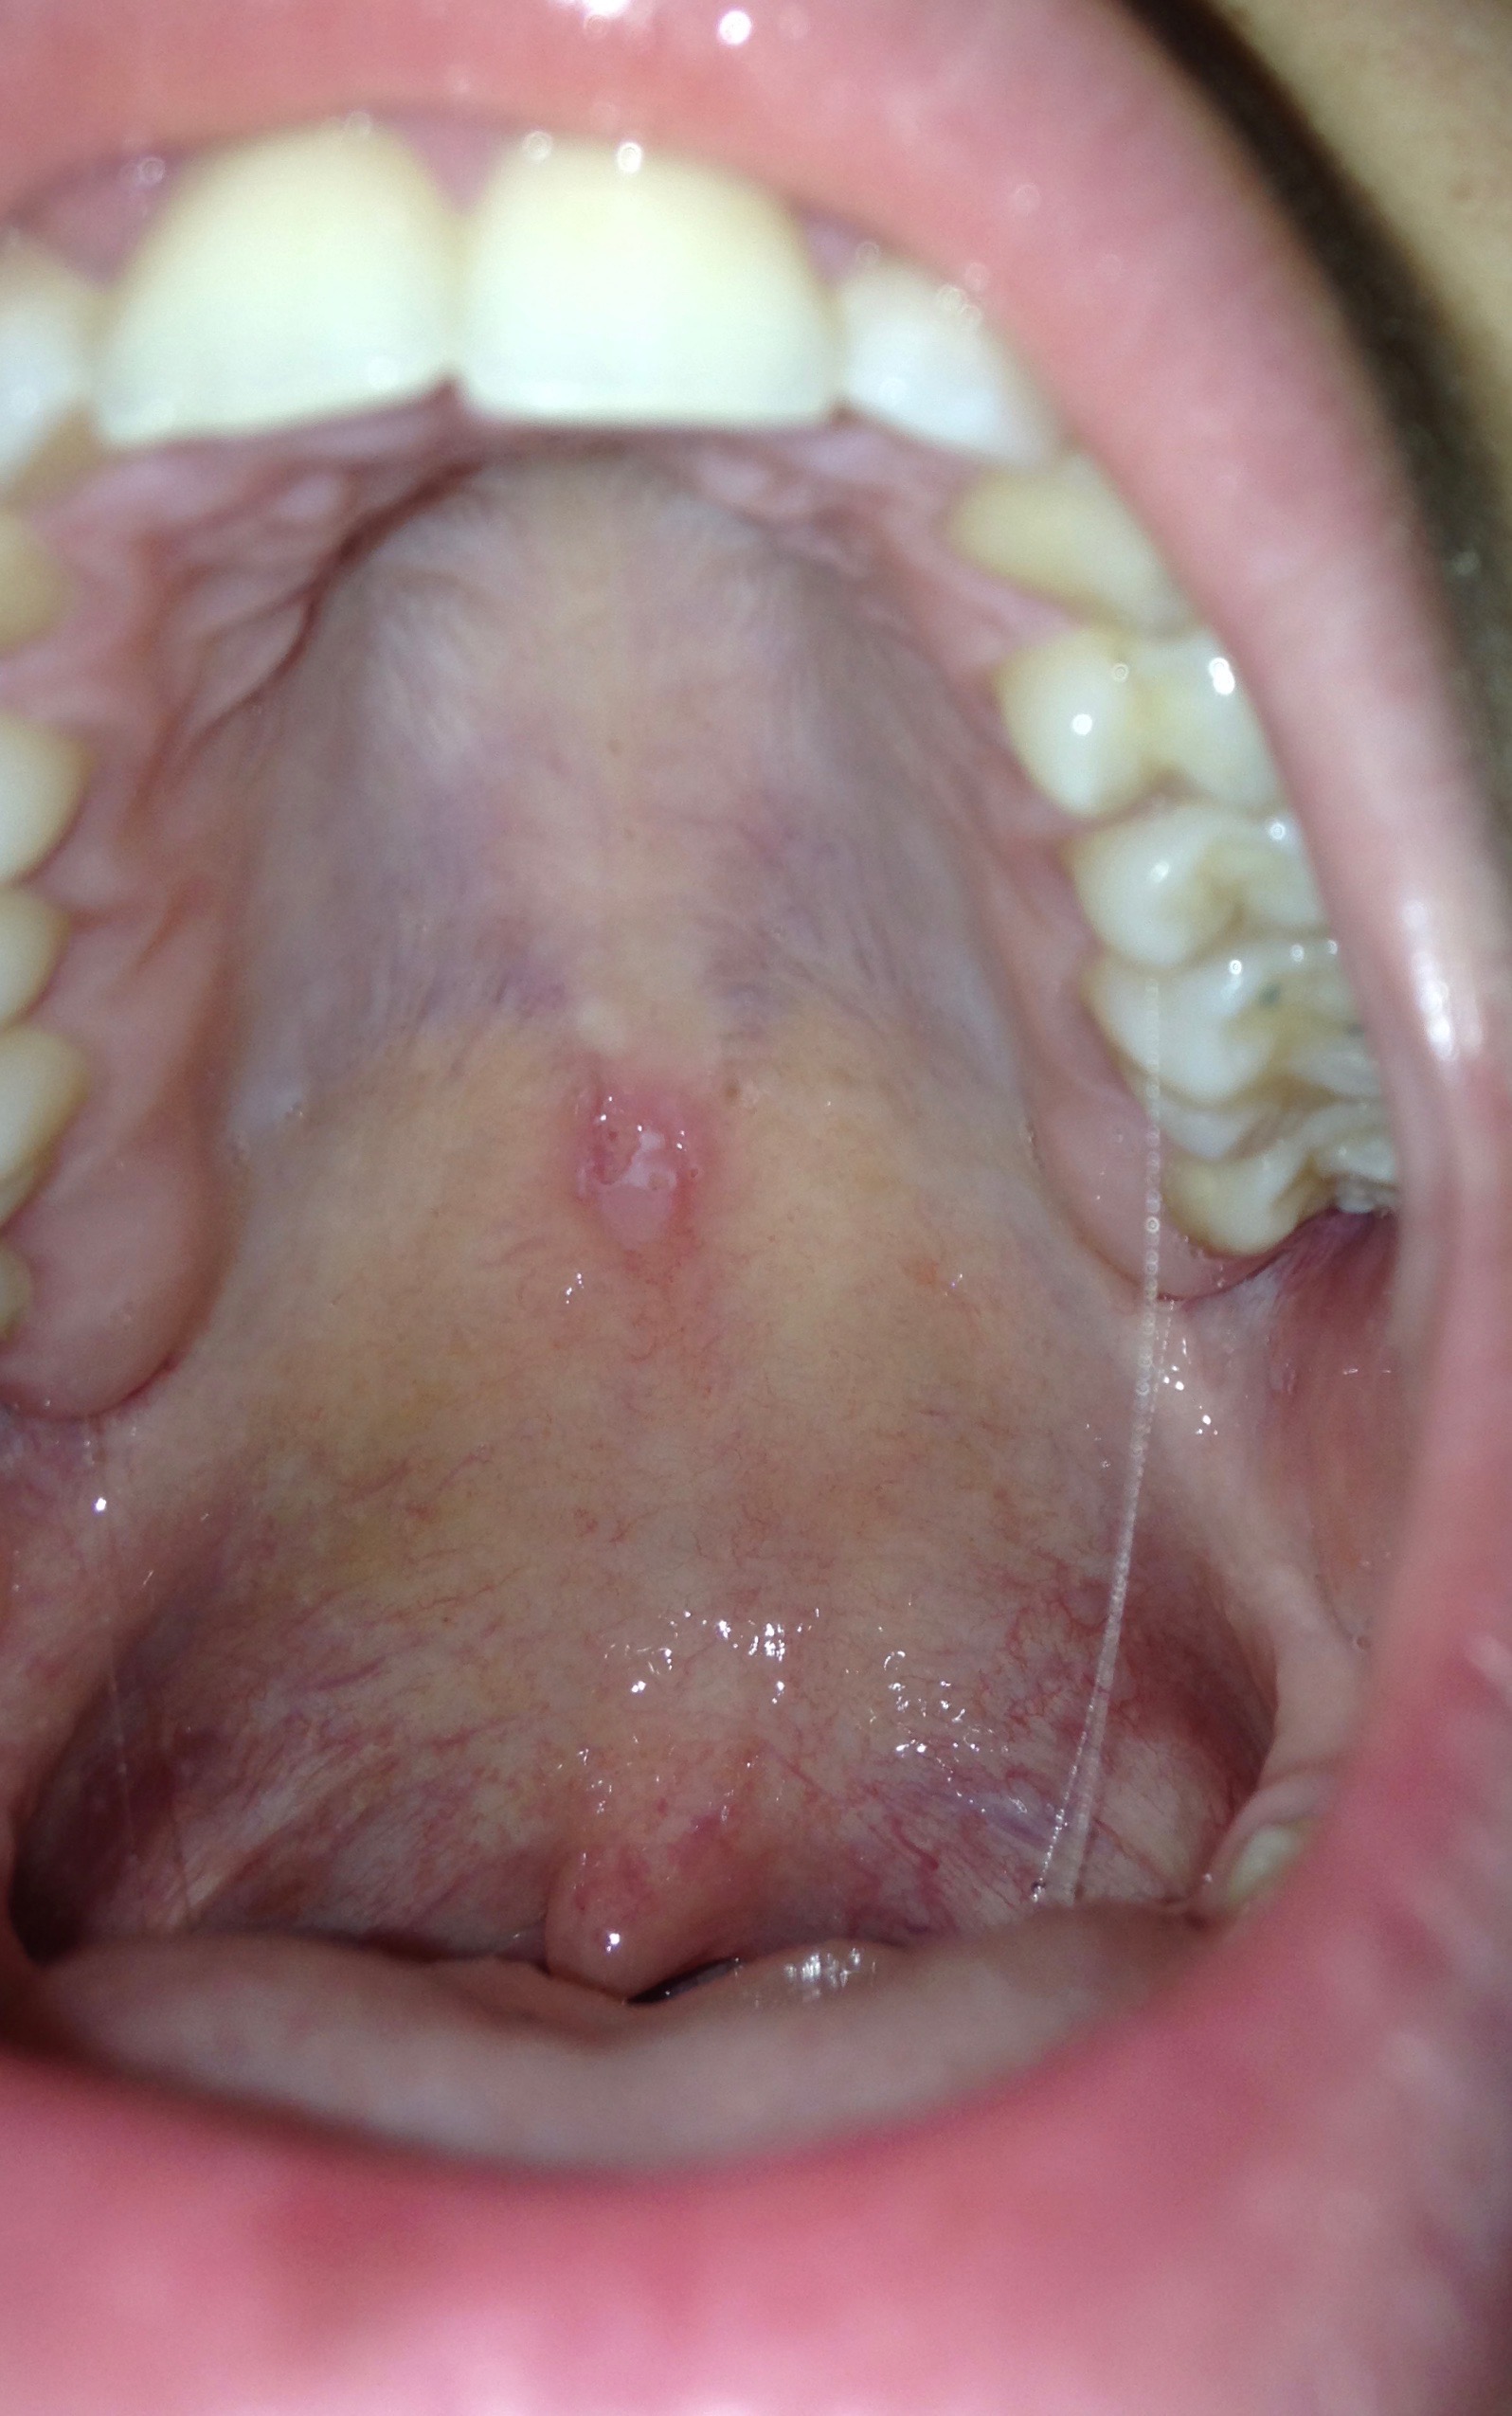

Buongiorno, sono un'igienista dentale. Da molti anni (la documento almeno dal 2013) ho una lesioni nel palato, tra il palato duro e molle. Ho eseguito tantissimi esami per cercare di capire cosa fosse e anche la biopsia. Ho eseguito tutti gli esami immunologici ed è tutto negativo! Anche RM e TAC non sanno dare una risposta. La lesione si presenta ciclicamente ma non con regolarità (a volte passa un mese altre volte anche 6-7 mesi prima che si ripresenti) e la durata anche è molto varia (da una settimana a un mese). Quando è presente è molto pruriginosa. Io ho anche una rinite autoimmune e nei periodi in cui faccio terapia con cortisone e antistaminico sto benissimo! Cercando un pò su internet ho trovato una lesione molto simile alla mia pubblicata sul vostro gruppo. Se qualcuno avesse mai visto qualcosa del genere e mi sapesse dire cosa possa essere ne sarei grata!

Potrebbe essere una forma papillomatosa da tenere sotto controllo, hai fatto hpv test?

Il fatto che abbia questa lesione da molti anni e che compaia saltuariamente può escludere patologie gravi come tumori ma esistono tante altre malattie anche importanti per le quali occorre fare una diagnosi differenziale. E' stata eseguita la Reazione di Wassermann? Ed il Test IGRA? Veda, nel suo caso l'anamnesi è molto importante oltre alla semeiotica medica che è parte della visita clinica e che serve per fare le Diagnosi Differenziali! Il problema è che l'anamnesi è costituita da una serie di domande anche molto personali, che il medico deve fare e non si possono certo farle pubblicamente on line! Si faccia visitare bene da un Dentista esperto in Patologia Orale (vada all'Università di Genova) e da un Dermatologo esperto in Malattie Veneree non perché ne sospetti una ma solo prudenzialmente! Si tranquillizzi. Faccia le analisi corrette e si faccia visitare dai professionisti giusti a Genova stessa perché possono occorre più incontri, analisi e prelievi! Cari saluti